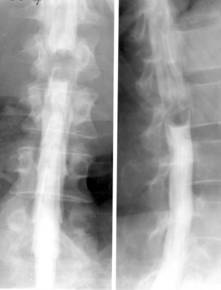

abcesul rece (pottic) apare ca o opacitate uni sau bilaterala ce proemina lateral, omogena, bine delimitata, depasind apofizele transverse. Abcesele din regiunea toracala medie nu migreaza la distanta si stagneaza in spatiul costovertebral sau intercostal, putand eroda coastele. Abcesele toracolombare coboara uneori pe teaca psoasilor in regiunea lombara, astfel ca vor modifica (bomba) umbra psoasului. Abcesele din regiunea cervicala deplaseaza anterior traheea si esofagul;